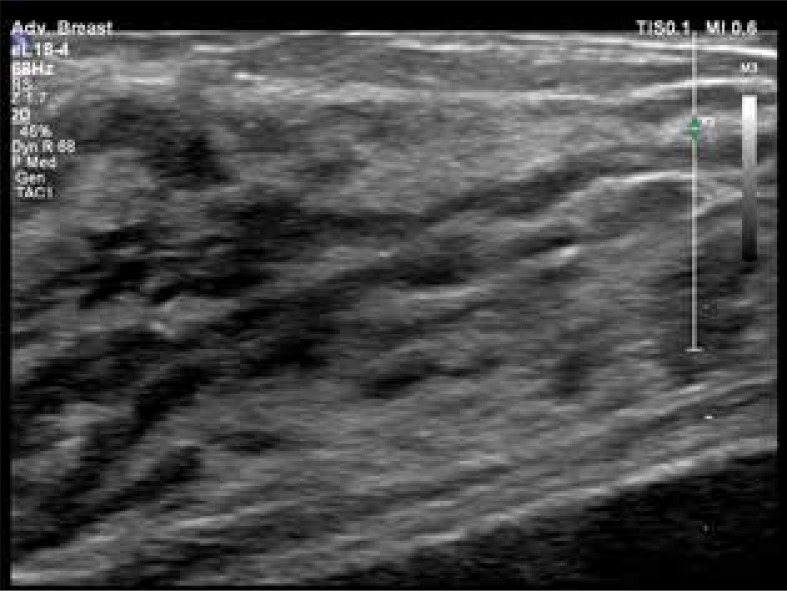

The intricate development and physiological dynamics of the mammary glands, orchestrated by a delicate interplay of hormones, are crucial for reproductive function and lactation. Beginning with intrauterine clusters evolving into mature glands, hormonal fluctuations throughout puberty and the menstrual cycle finely tune mammary tissue growth. Oestrogens stimulate the proliferation of epithelial cells, while progesterone orchestrates the formation of lactiferous glands. During pregnancy, oestrogen and progesterone induces hyperplasia of lobules and ducts, preparing the breast for lactation. Prolactin is vital for lactation and stimulates milk production during pregnancy and postpartum. As shown by ultrasonography, physiological changes during lactation reflect glandular tissue transformation for milk secretion. Clinical and physiological changes, including increased blood flow, contribute to mammary growth and firmness, complicating clinical examination. Ultrasonographic findings reveal variability in women's glandular and fat tissue distribution, suggesting that milk production is not solely determined by anatomical factors. Though not directly linked to milk production, blood flow dynamics hint at a threshold for optimal lactation. Understanding these complex hormonal and physiological mechanisms is crucial for comprehending mammary development, function, and clinical assessment.